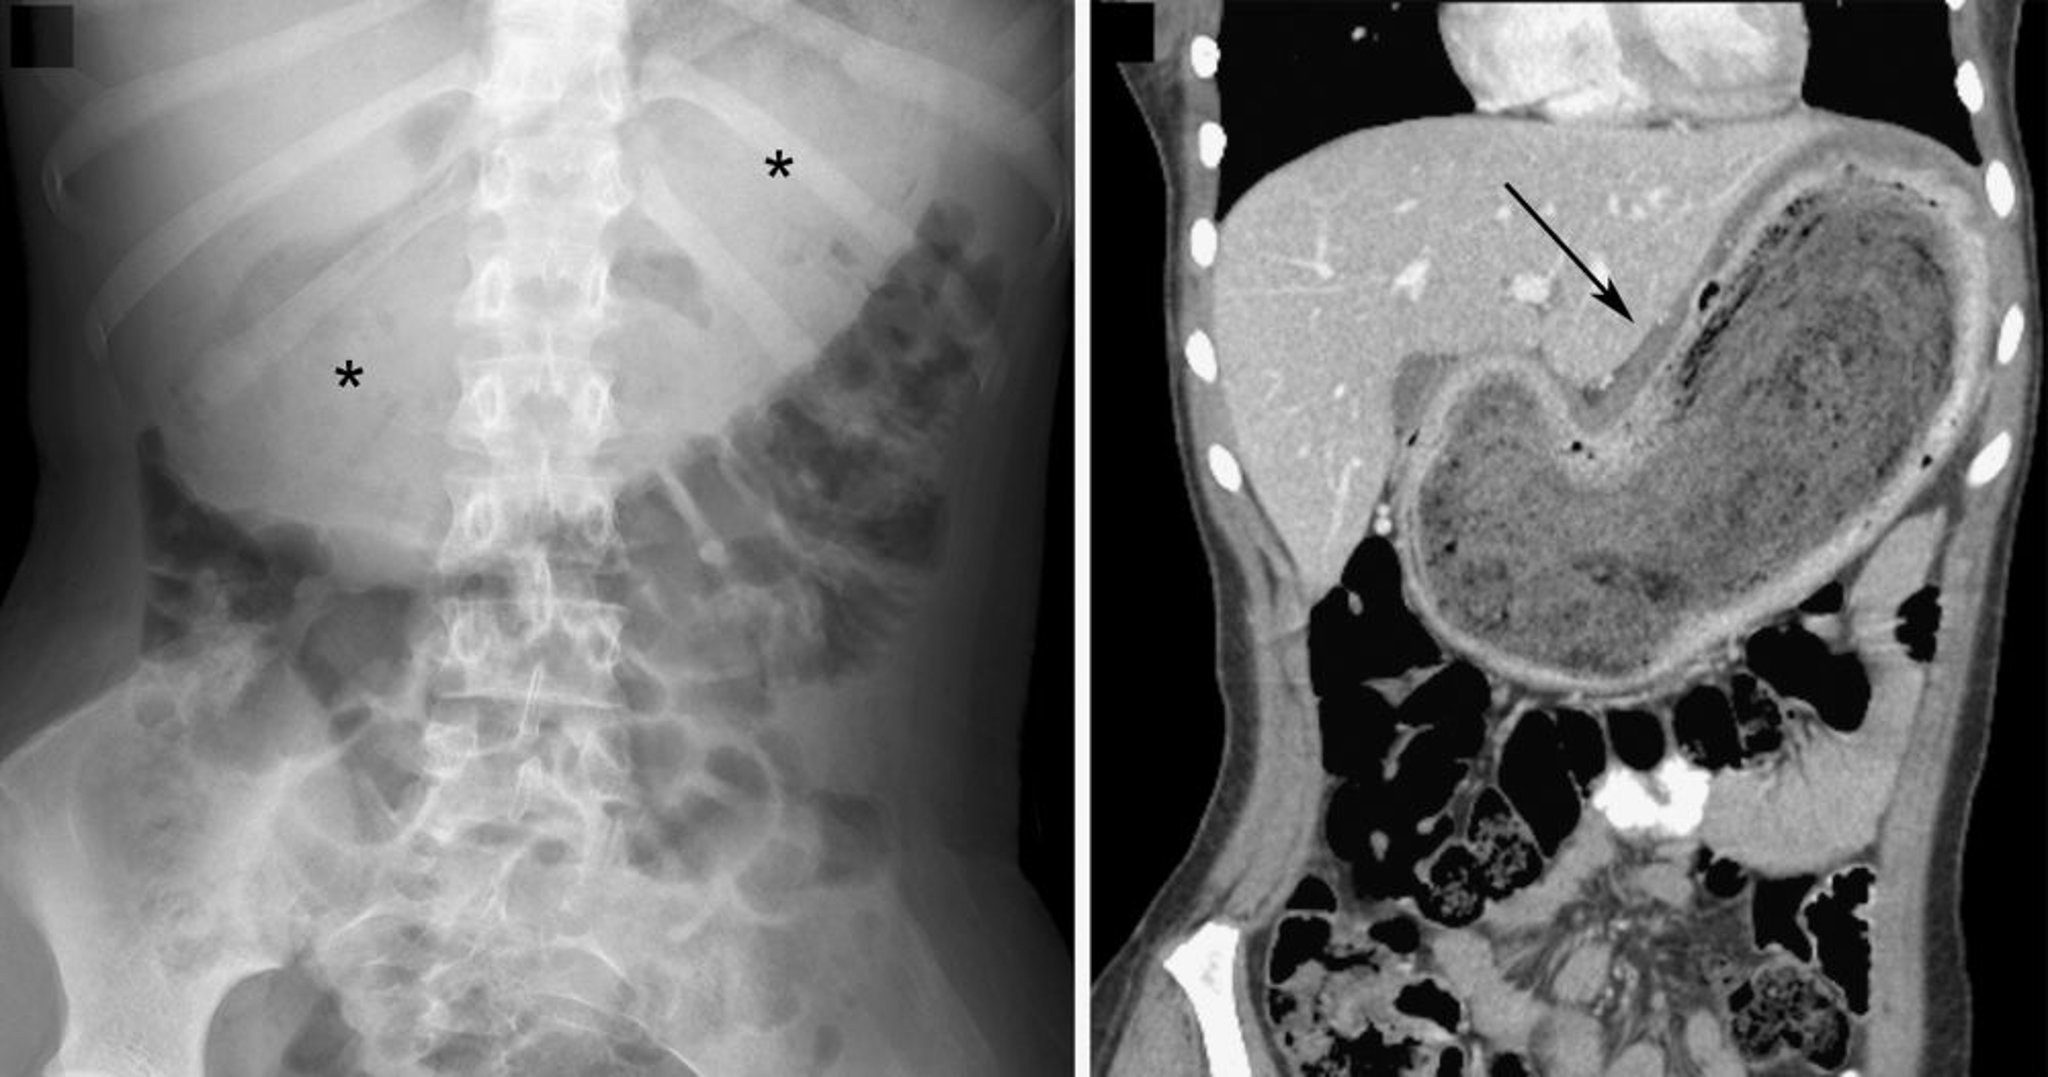

Bézoar (Signe d'imagerie)

Sur l'image radiographique de gauche, le bézoar est indiqué par la volumineuse masse des tissus mous située sur la ligne médiane de la partie supérieure de l'abdomen, présentant un aspect tacheté avec du gaz intralésionnel (astérisques). Dans l'image TDM coronale à droite, le bézoar est indiqué par la masse hétérogène (flèche). Dans les deux images, on observe un déplacement inférieur des anses intestinales.